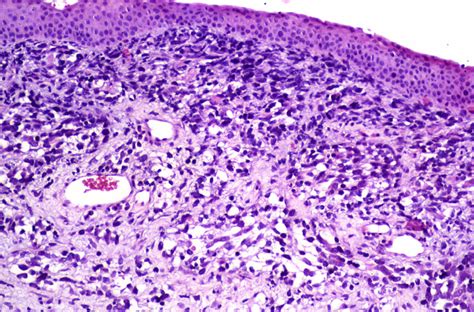

Microscopía de rabdomiosarcoma